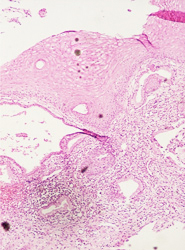

El resultado de una valoración colposcópica de paciente con lesión displásica siempre será confirmado por el estudio histopatológico que realiza el médico anatomopatólogo (estudio de la biopsia tomada en la colposcopía) . A continuación presentamos imágenes histológicas con sus diagnósticos.